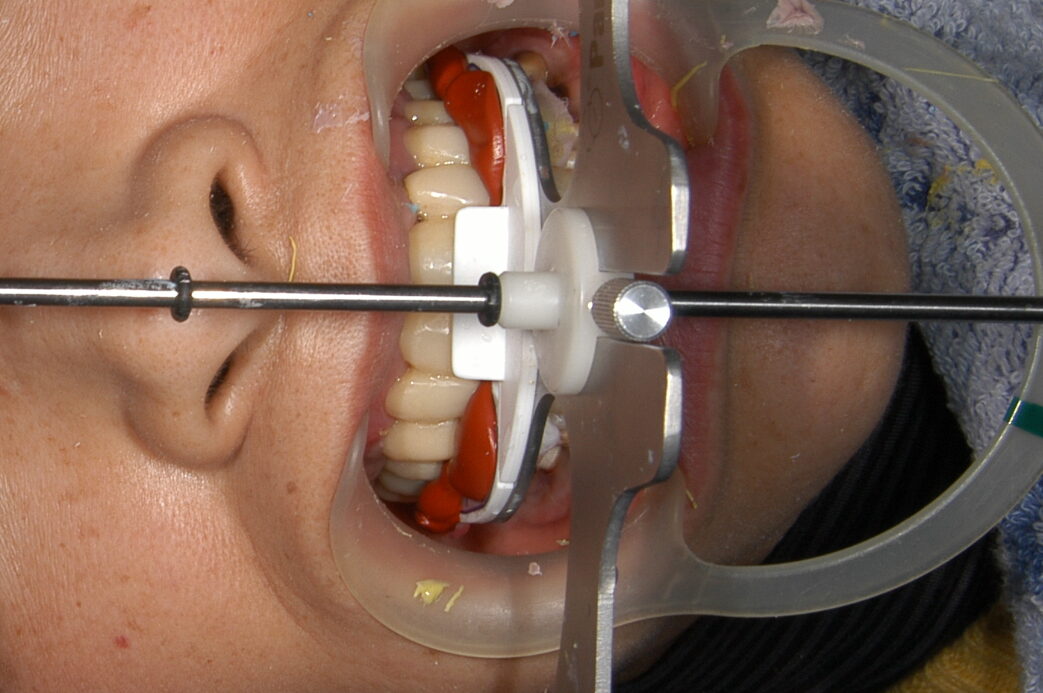

治療中③ このように多数歯の被せ物を作製する際には咬合も精密に採得して技工所に送ります

ただただ作製するのではなく、審美面でも機能面でも長く使っていただけるように設計していきます